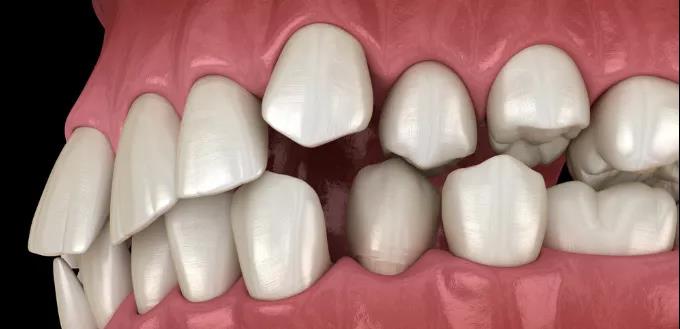

5、咬合紊乱

同侧智齿没有长出或已经拔除,没有对位的智齿正常咬合的话,可能会出现智齿过度生长的情况。

牙齿错位咬合

从而咬到对侧的牙床,形成错位咬合。

6、矫正畸形牙齿

因为需要排齐牙齿的位置,确保正畸治疗的效果,一般会考虑拔掉智齿。

假如是智齿占用空间引发的牙齿排列错乱不齐,甚至变形,就更需要拔了。